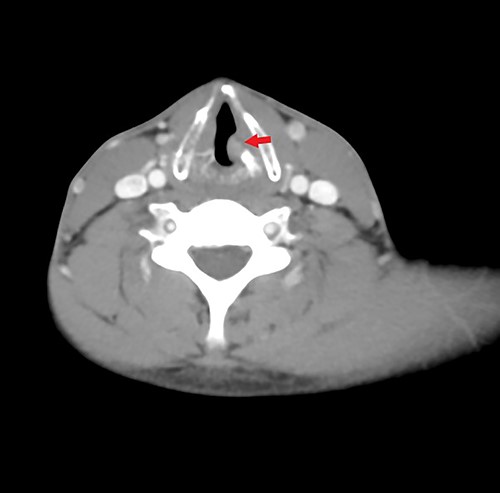

Computed tomography (CT) scan with contrast was ordered and showed an ill-defined heterogeneous enhancing left glottic versus supraglottic mass minimally extending to the laryngeal ventricle associated with sclerosis of the left arytenoid cartilage. It measures 2 × 0.5 × 1 cm in craniocaudal, transverse and anterior–posterior dimensions (Fig. 2). However, there was no associated invasion into the subglottic space nor paraglottic space. No pathologically enlarged cervical nor supraclavicular lymph nodes were seen.

Axial contrasted CT image of larynx, showing left sided glottic versus supraglottic mass.